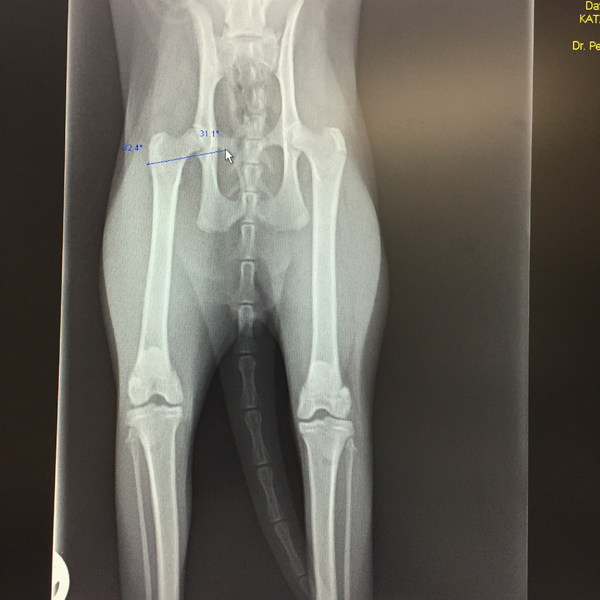

X-ray imaging remains an invaluable diagnostic tool, offering essential insights into heart, lung, digestive, and urinary tract diseases. For skeletal evaluations—whether assessing fractures, degenerative changes, growth abnormalities, or congenital malformations—X-rays are still the preferred method.